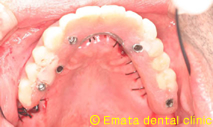

All-on-4(オールオンフォー)とは従来のインプラント治療に大きな変革をもたらす、画期的で最新の治療方法です。たった4本から6本でインプラントで12本分の歯を支えることを可能で手術が終わったとたんに入れ歯から開放され、固定式の歯がはいります。

| All-on-4は4本ではないかとおもいますが、骨の状態や対合歯が自分の歯なのでより確実性をもたせたいため5本で立ち上げ、2本はスリープさせました。

この症例のポイントは、ソケットリフト部位への即時負荷でしょう。アダプテーションテクニックにより40ニュートンの初期固定がえられました(専門的になってしまいましたね)。 麻酔専門医の先生が静脈内鎮静法を行っていますので患者さんは半分寝ているうちに手術が終わってしまいます。 |

仮歯までいれるのに半日かかりましたが、患者様には大変喜んでいただきました。 |